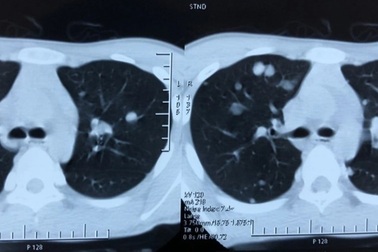

Các triệu chứng của ung thư di căn phổiCác loại ung thư thường di căn đến phổi bao gồm ung thư vú, ruột kết, trực tràng, đầu và cổ, thận, tinh hoàn và tử cung cũng như ung thư hạch bạch huyết.

Ung thư tuyến giáp di căn phổi chữa được không?Ung thư tuyến giáp di căn, còn được gọi là ung thư tuyến giáp giai đoạn 4, là khi ung thư đã lan từ tuyến giáp đến các vùng xa của cơ thể. Phổi là cơ quan di căn xa phổ biến nhất.